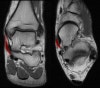

3. Posterior Talofibular ligament

Coronal (left) and axial (right) T1W images assessing the normal posterior talofibular ligament. This ligament is normally less dark than the anterior talofibular ligament.